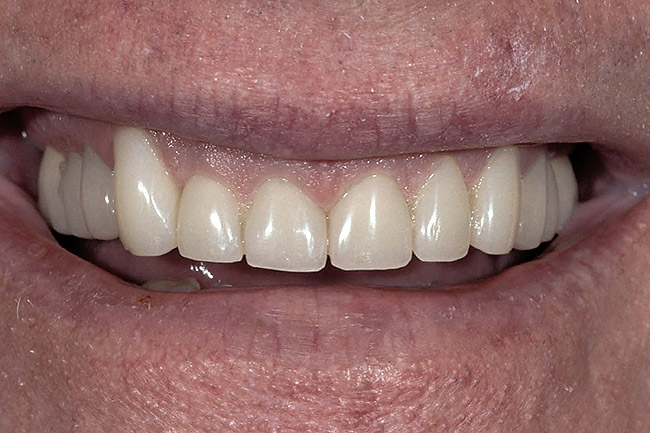

Figure 10  The final restorations demonstrate the esthetic and functional changes from lengthening the incisal edges and raising the gingiva.

Figure 10